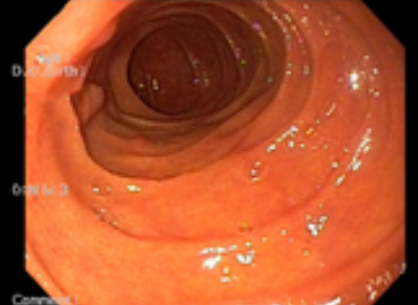

위내시경 검사는 위나 십이지장, 식도를 내시경 카메라로 살펴보는 검사로 평소 소화가 잘 되지 않거나 더부륵함, 메스꺼움, 복통, 속 쓰림, 구토 증상 등이 있다면 위염, 역류성식도염, 위용종, 위궤양, 위출혈, 십이지장질환, 위암, 식도암 등이 있을 수 있으므로 꼭 해보는 것을 권장드립니다.

위내시경 검사의 방법은 수면과 비수면으로 진행되는데 비수면 위내시경 검사의 소요 시간이 5분~10분 정도밖에 걸리지 않아 빠르고 간편합니다. 비수면 위내시경 검사의 경우 직접 본인의 위 상태를 직접 눈으로 볼 수 있어 조금 더 위 건강에 신경 쓸 수 있다는 장점이 있습니다.

위내시경 검사 중 조직검사를 통해 헬리코박터 감염 여부도 확인할 수 있습니다. 헬리코박터 파일로리 균 검사의 경우 1~2일이 지나면 결과를 알 수 있고, 조직 검사의 경우 7일에서 10일 정도 후 감염여부를 알 수 있습니다. 한 의료기관에서 위내시경 검사를 받았다면 2년 뒤에도 같은 병원에서 정기적으로 진행하는 것이 환자한테 좋습니다.